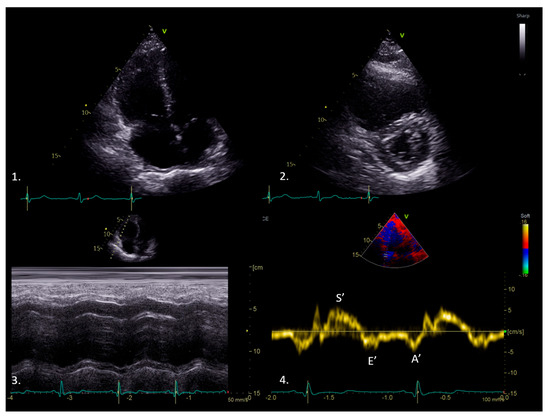

3. Tissue Doppler Imaging Characteristics